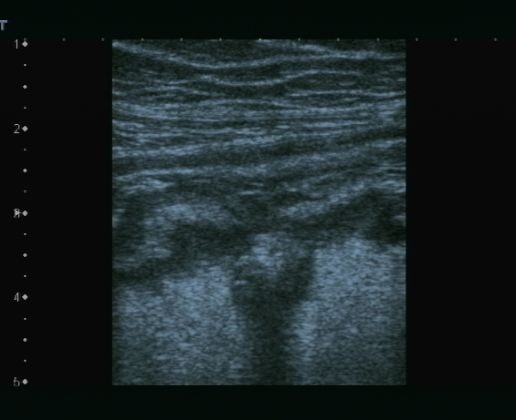

Lo studio medico privato del Dottor Patrizio Stornelli è ad Avezzano è dotato di un'attrezzatura ecografica moderna. Oltre alla ecografia addominale dei parenchimi, si esegue l'ecografia gastroenterolgica ed in particolare l'ecografia del tenue, che consente la diagnosi ed il follow-up particolaremente dei paziente con malattia di Crohn, ma anche l'ecografia del colon. Grazie a questo approccio è possibile scansionare interi segmenti del colon con particolare riguardo alla patologia diverticolare ma anche di indiduare l'appendice e di porre diagnosi di certezza di eventuale appendicite acuta.

Particolare importanza per lo studio delle patologie focali epatiche, è l'ecografia epatica con mezzo di contrasto o CEUS. La metodica unitlizza ultrasuoni a basso indice meccanico e un ecoamplificatore rapresentato da microbolle iniettate in vena; questo sistema permette in real time la stessa semeitoca TAC o RMN per lo studio delle lesioni focali epatiche.

Oltre all'ecografia gastrointestinale, l'ecografia tiroidea rappresenta un altro campo specialistico di vasta esperienza con esecuzione della diagnostica base, il colordoppler e doppler tiroide e lo studio elastografico delle lesioni nodulari tiroidee altrimenti detta elastografia. Questa metodica permtte lo studio della elasticità dei tessuti e considerando che i tessuti neoplastici tendono ad essera di consistenza aumantata, l'elastografica ci aiuta a selezionare i noduli da sottoporre ad campionamento citologico con FNAB.